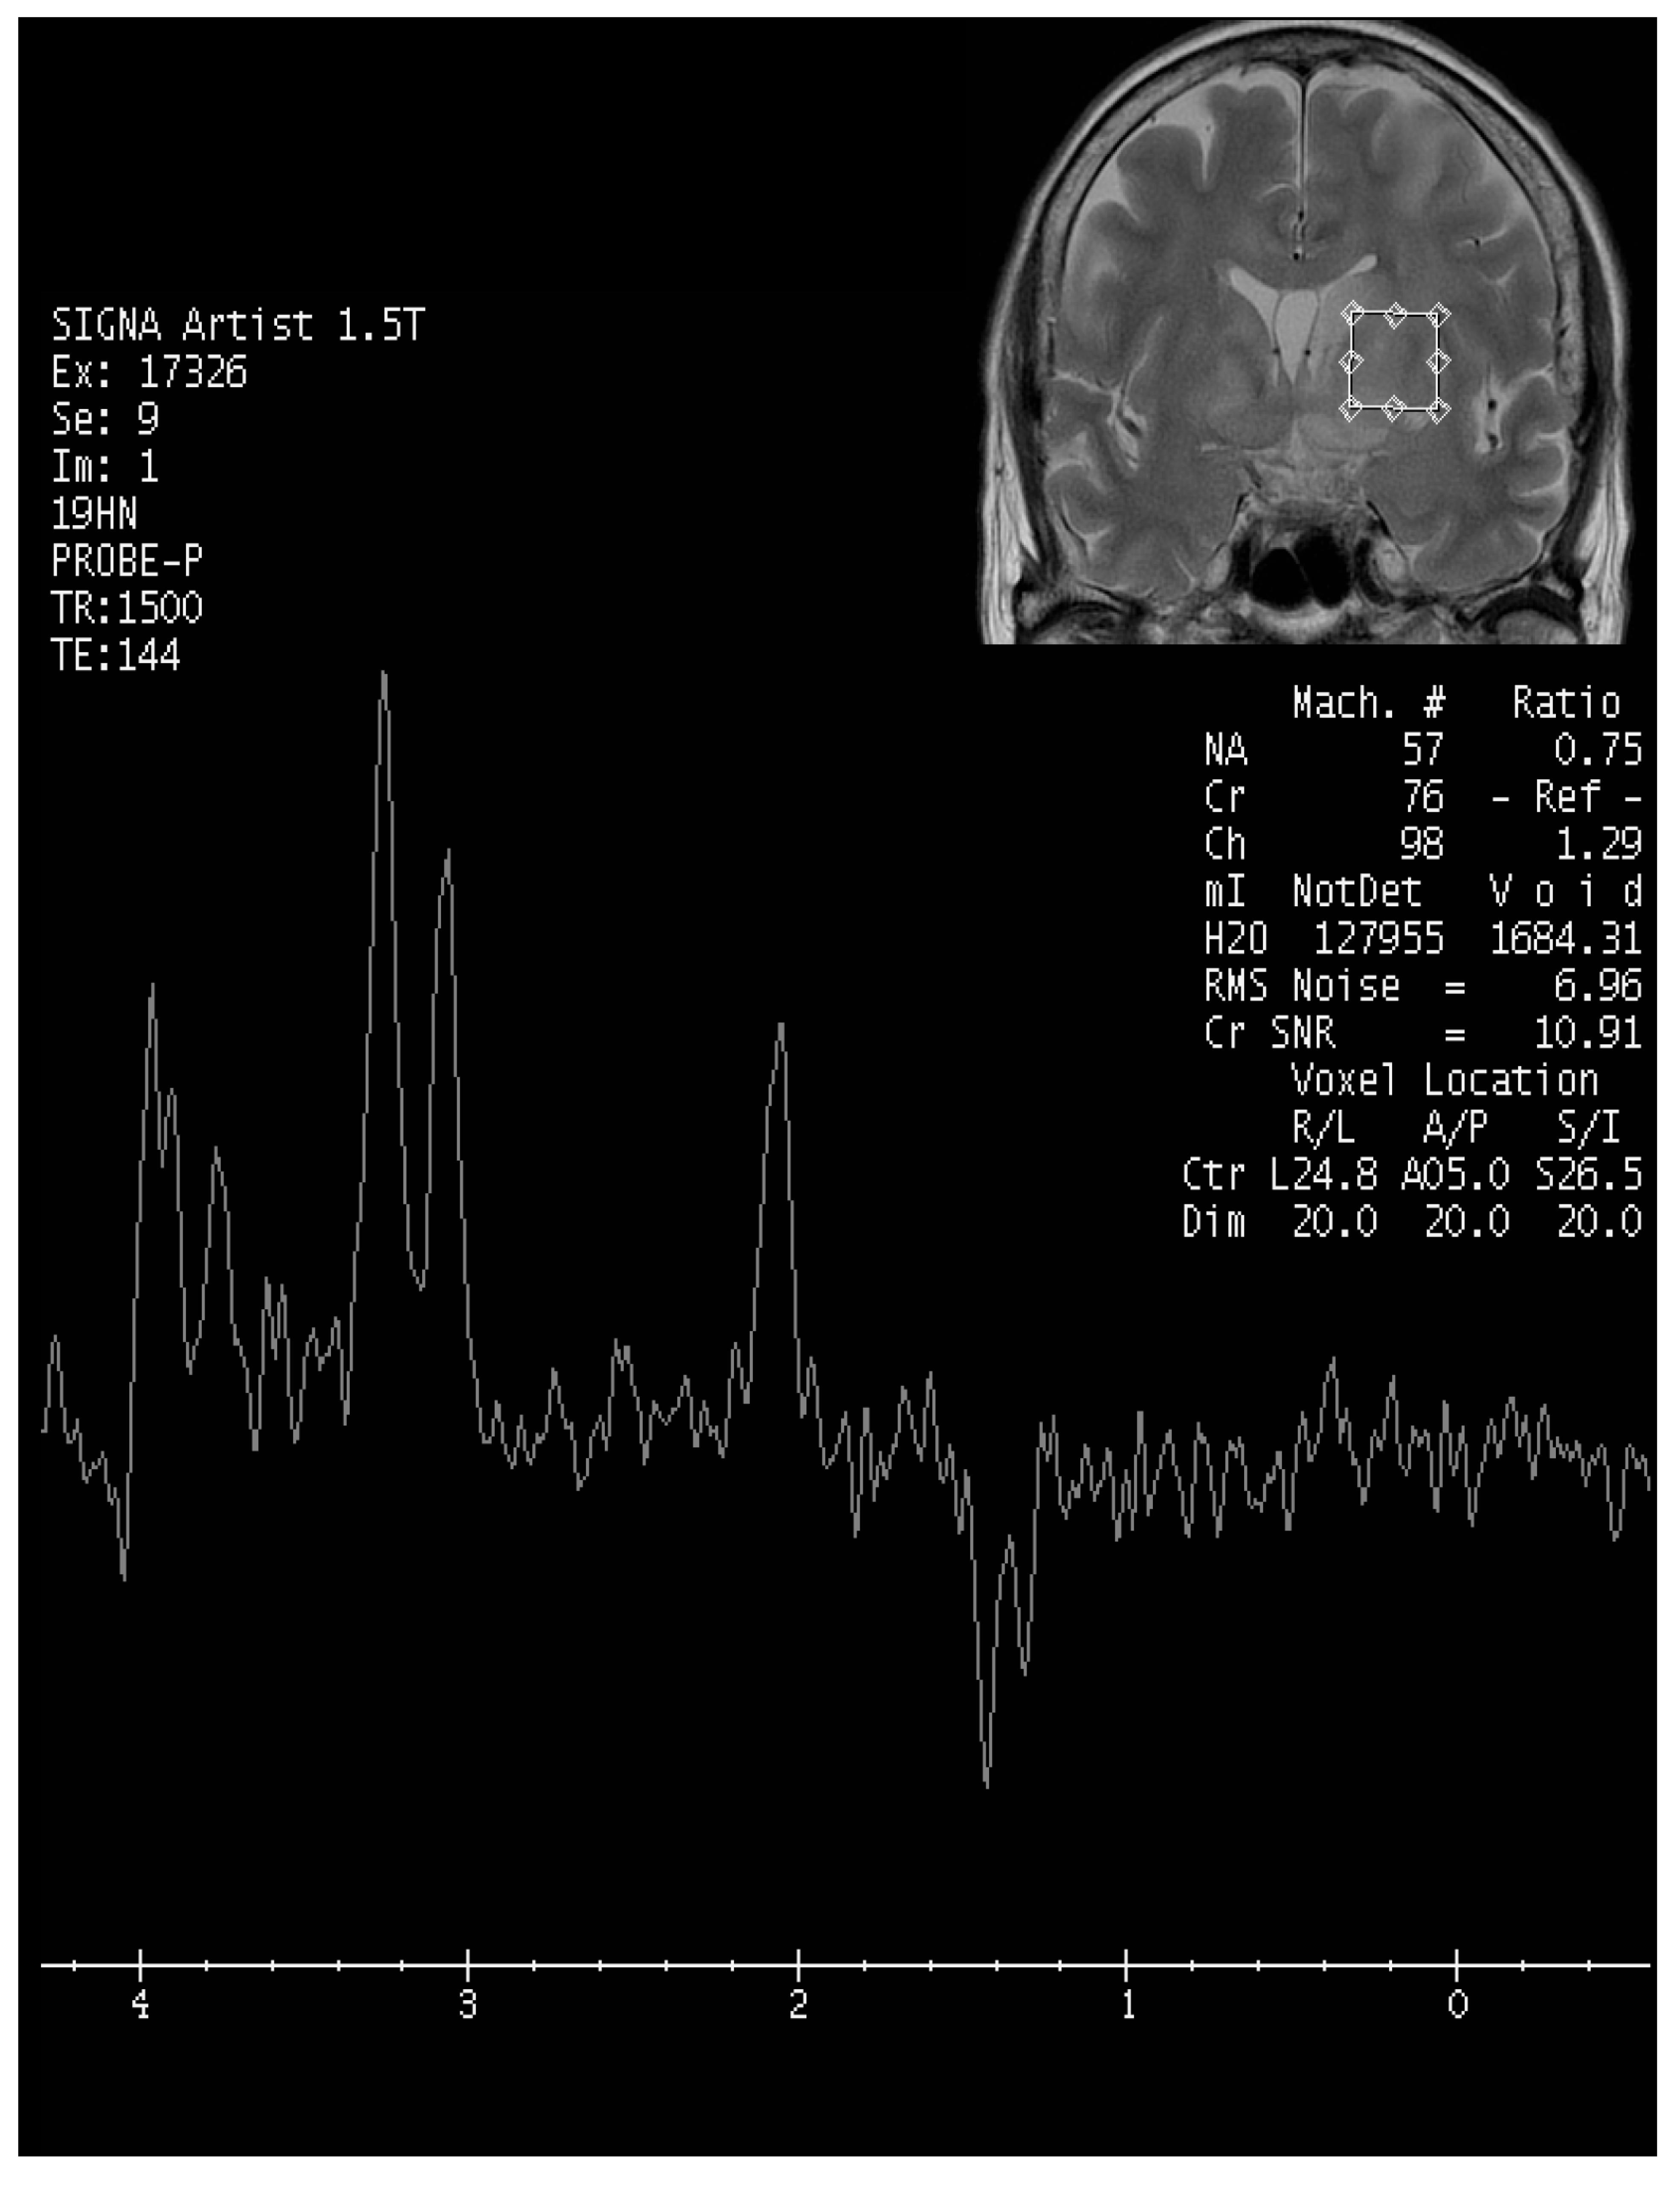

Upon evaluation, her fever persisted at 38.2 degrees Celsius, and laboratory investigations revealed leukopenia with a white blood cell count (WBC) of 610/μL. The urinalysis showed no evidence of pyuria, and the chest X-ray results were unremarkable. The treatment included the administration of Granulocyte Colony-Stimulating Factor (GCSF) for leukopenia and empirical antibiotics, specifically piperacillin/tazobactam, to address the neutropenic fever. An extensive infectious workup was conducted on admission, including a cerebrospinal fluid (CSF) analysis, which did not identify a clear infectious focus. The blood cultures yielded no bacterial growth. The patient’s WBC count elevated to 7430/μL after GCSF treatment. However, intermittent fever was still observed. Six days after admission, she exhibited a slow response and developed right-sided weakness. A relapse of CNS lymphoma or other CNS lesion was suspected. A brain computed tomography (CT) scan revealed abnormal hypointense changes in the left frontal lobe, left basal ganglion, left thalamus, and left cerebral peduncle with associated brain swelling (Figure 1). The subsequent magnetic resonance imaging (MRI), performed three days later, revealed hyperintensity in the left frontal and left parietal lobes, bilateral corona radiata, basal ganglia, and thalami, as well as the left temporal lobe and left-side brainstem on T2 weighted images (T2WIs), fluid attenuated inversion recovery (FLAIR), and diffusion weighted images (DWIs) without obvious restricted diffusion. No definite contrast enhancement was observed on the post-gadolinium T1 weighted images (Gd-T1WIs) (Figure 2). The presence of a mass effect from the infiltrative lesions, resulting in the compression of the left lateral ventricle and a midline shift to the right side, was observed. Notably, magnetic resonance spectroscopy (MRS) focused on the left basal ganglion lesion showed an elevated choline peak and decreased N-acetylaspartate (NAA) peak, with the presence of a lactate peak (Figure 3). A stereotactic brain biopsy for the left basal ganglion lesion and the left frontal lobe lesion confirmed the presence of diffuse large B-cell lymphoma, and the patient subsequently received whole-brain radiotherapy. Following treatment, the patient’s consciousness improved to an alert state (E4V5M6), and her right limb muscle strength showed improvement. Under stable conditions, she underwent another cycle of R-CHOP chemotherapy and completed whole-brain radiotherapy (WBRT). The patient was transferred to a nursing home under a stable clinical condition.

Figure 3. MR spectrocopy focusing on left basal ganglion lesion. Elevated choline peak and decreased N-acetylaspartate peak, with the presence of a lactate peak were found.